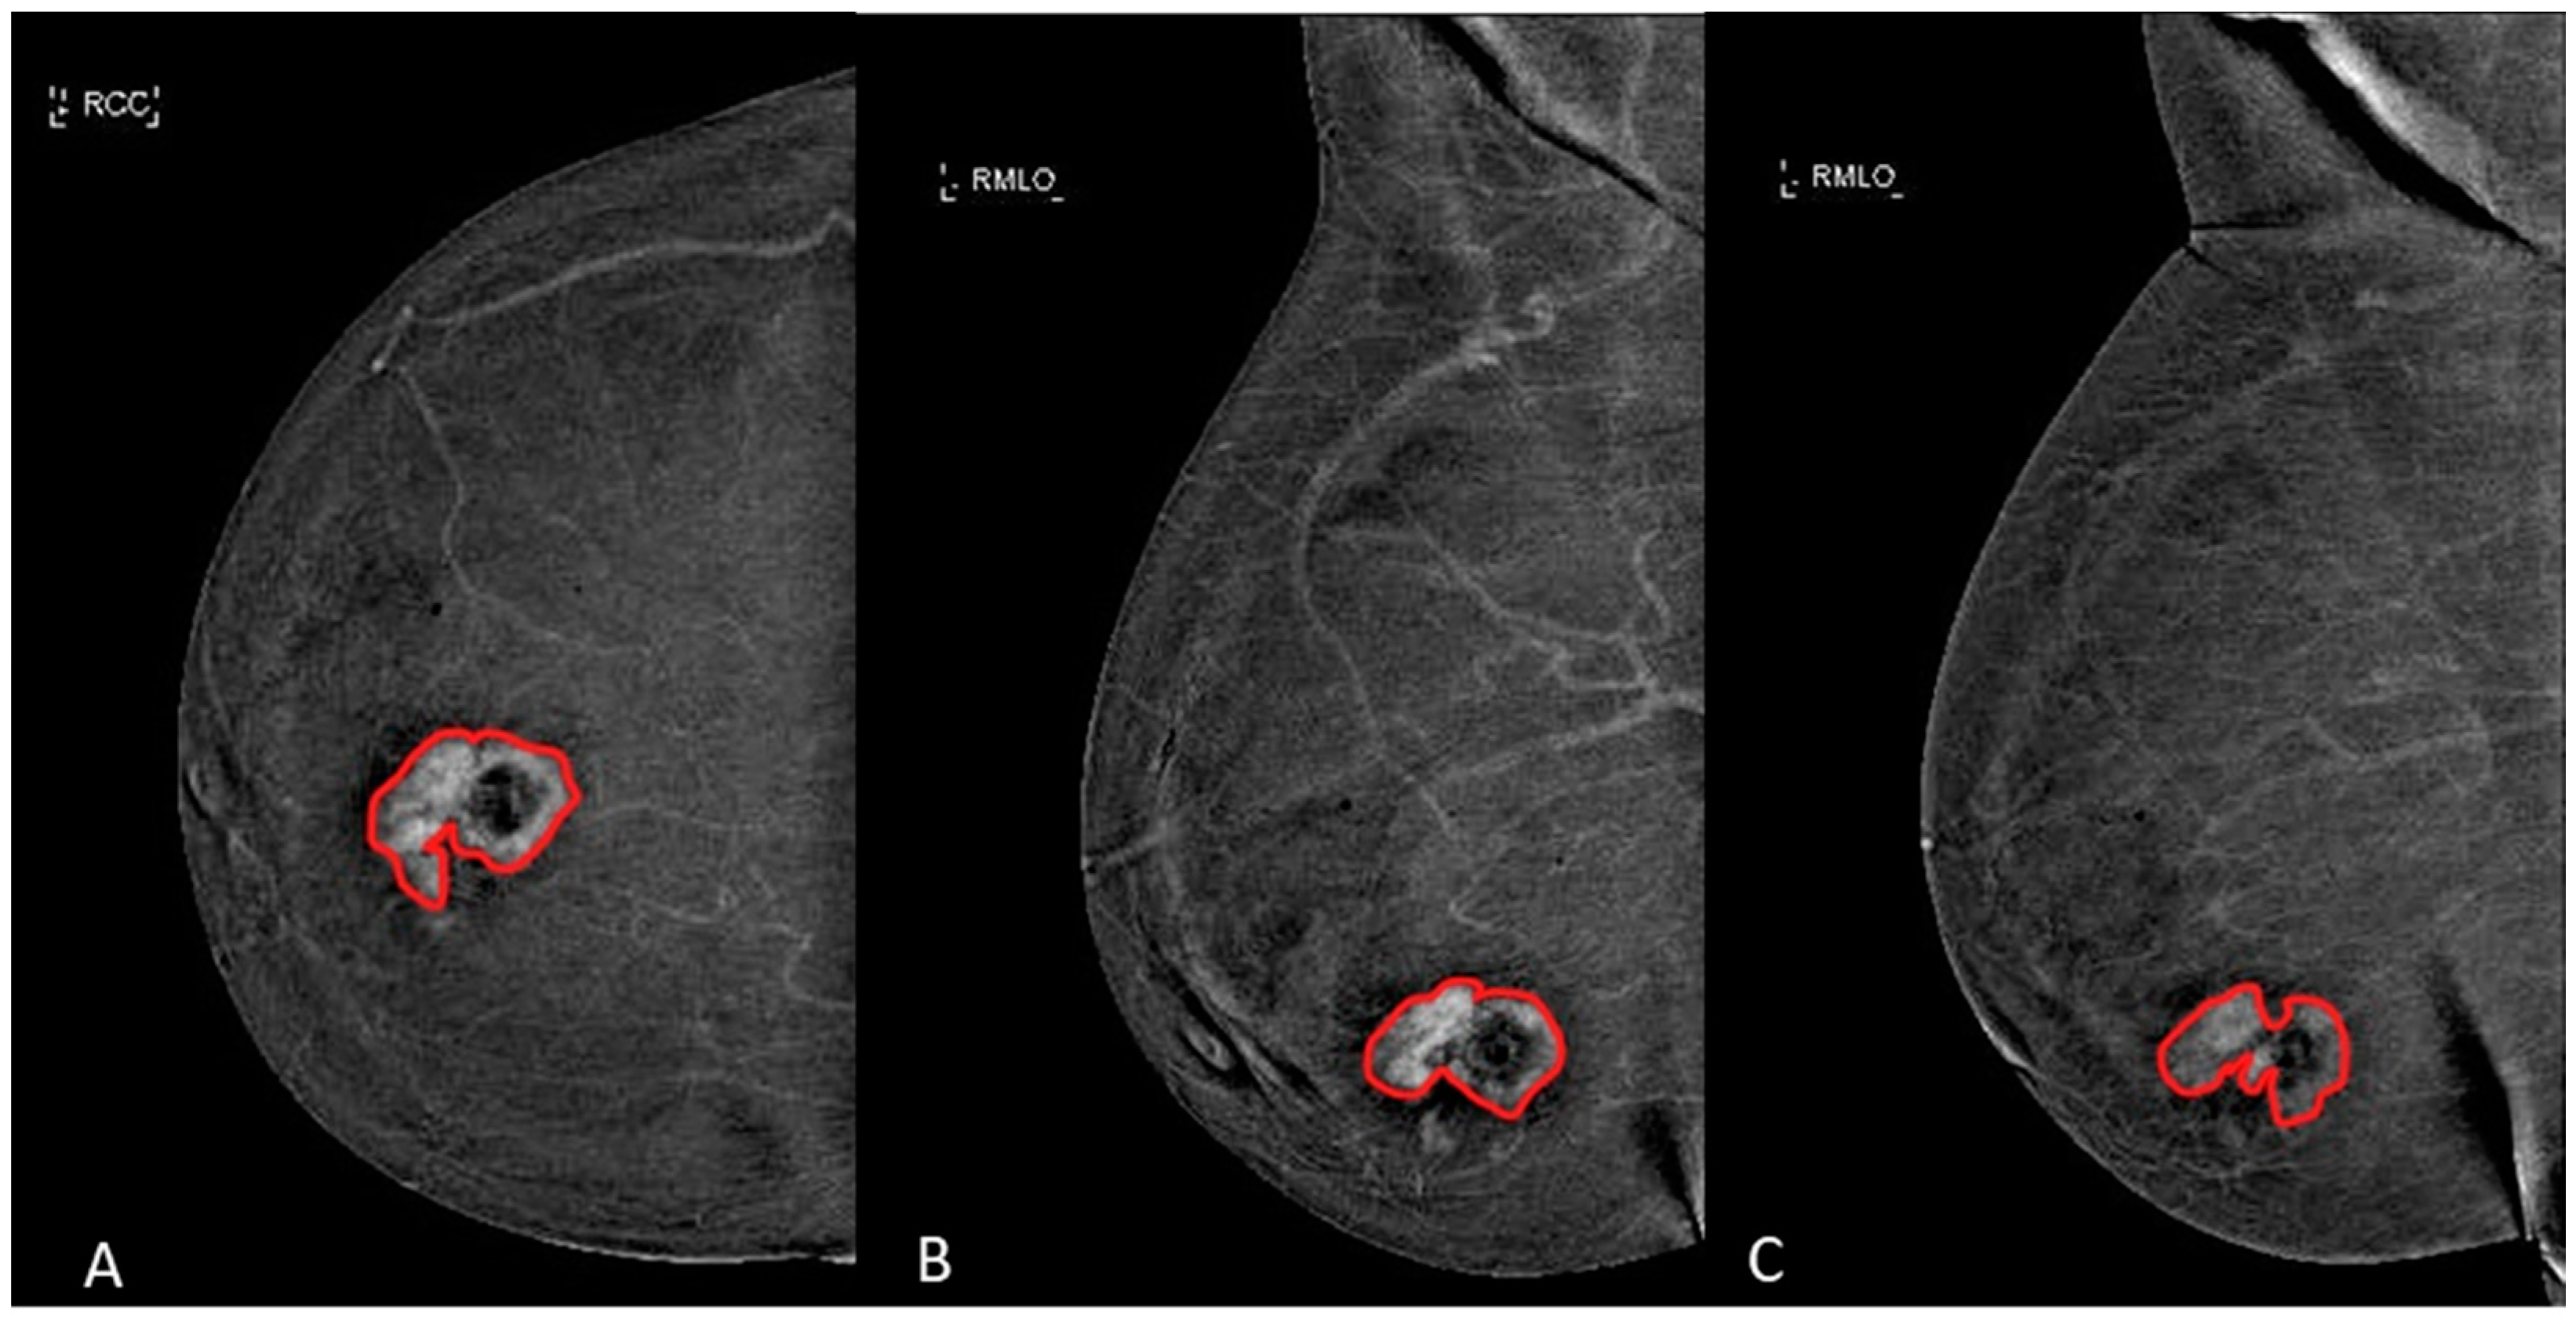

The margins of the breast lesions were defined on dual-energy subtracted (DES) images, where contrast uptake was emphasized, both in CC and in early and late MLO view. An example is shown in Figure 2.

Figure 2.

Manual segmentation (red line) of an ILC in a 58-years-old woman with dense breast in (A) CC view, (B) early MLO view and (C) late MLO view.